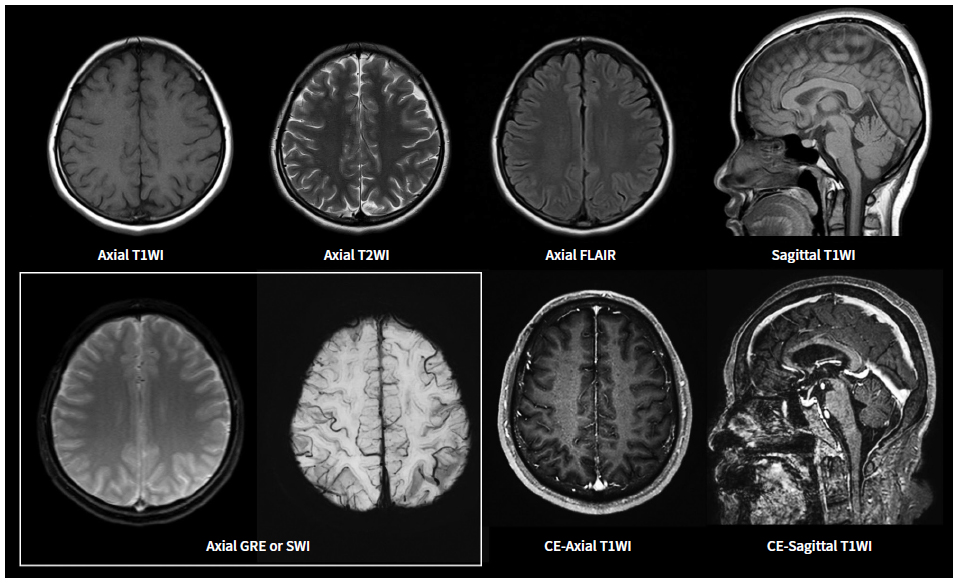

MRI(자기 공명 영상)은 강력한 자기장과 라디오파를 이용하여 체내 조직의 이미지를 생성하는 기술입니다. MRI는 연부 조직, 즉 뇌, spinal cord, 근육, 그리고 다양한 내장 장기 등을 상세하게 볼 수 있는 특징이 있습니다. 주로 신경계, 근골격계 및 종양 연구의 진단 도구로 사용됩니다.

MRI는 인체 내의 수소 원자의 자기적 성질을 이용하여 이미지를 생성합니다. 강력한 자기장이 수소 원자를 정렬시킨 후, 라디오 파를 통해 이들을 자극하여 방출되는 신호를 수집합니다. 수집된 신호는 컴퓨터에 의해 해석되어 이미지를 만들어 내는데, 이 과정에서 세부적인 이미지가 생성되어 체내 구조를 명확하게 볼 수 있게 됩니다.

MRA는 MRI의 기법을 기반으로 하므로, 기본적으로는 동일한 작동 원리를 가지고 있지만, 약간의 차이점이 있습니다. MRA는 특히 혈관을 시각화하는 데 최적화되어 있으며, 주로 조영제를 사용하여 혈관을 더욱 뚜렷하게 구분합니다. 조영제는 혈관 내에서 신호의 차이를 만들어 신호 강도를 높여줍니다. 이로 인해 혈관의 형태와 상태를 더욱 명확하게 시각화할 수 있습니다.